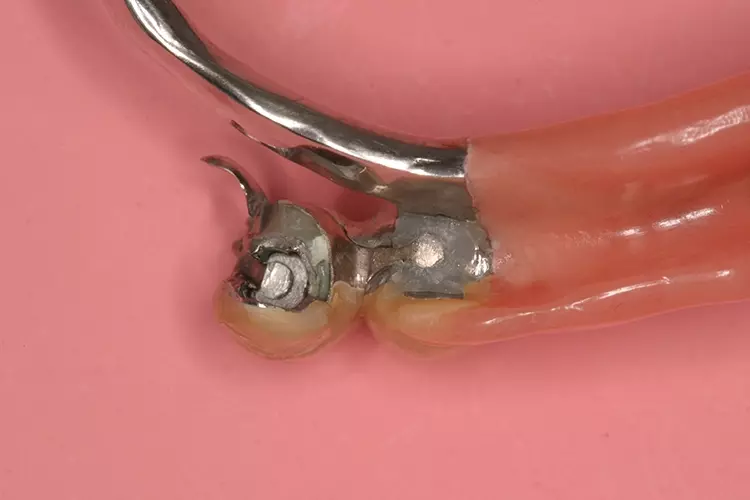

Als relative Kontraindikation sind karies- und restaurationsfreie Pfeilerzähne mit zervikalen keilförmigen Defekten über 1 mm Tiefe zu nennen, da diese zu einer erhöhten Frakturgefahr des Pfeilerzahnes bei Belastung führen. Adhäsivattachments können zur Reparatur vorhandener Doppelkronen- oder Geschiebearbeiten verwendet werden, sofern der verbliebene Nachbarzahn einer verloren gegangenen Doppelkrone karies- und restaurationsfrei ist. Die Matrize wird in diesem Fall in die ausgeschliffene Doppelkrone oder in die Geschiebekrone des verlorenen Pfeilerzahns eingeklebt (Abb. 1 bis 4).

Adhäsivattachments werden in der Regel aus Cobalt-Chrom(CoCr)-Legierungen hergestellt. Um eine ausreichende Steifigkeit des Materials zu gewährleisten, sollte eine Mindeststärke des Adhäsivflügels von 0,7 mm eingehalten werden. Die Ränder sollten möglichst auf Minimalstärke ausgearbeitet werden.

Die Klebefläche sollte mindestens 30 mm2 betragen. Empfohlen werden kostengünstige extrakoronale, semipräzise Stabgeschiebe mit auswechselbaren Kunststoffmatrizen (z.B. Preci-Vertix, Fa. Ceka, Hannover). Um Frakturen zu vermeiden, sollten die Geschiebestäbe extrakoronal mit einer Mindestverbinderhöhe von 3 mm zwischen Stabgeschiebe und Adhäsivflügel konstruiert werden. Die auf 3 mm kürzbaren Geschiebestäbe sollten parodontalfreundlich mit einer Führung für Interdentalraumbürstchen durch eine direkte, ponticförmige Auflage auf dem Kieferkamm angebracht werden.

Eine Kippmeiderfunktion und erhöhte Rigidität des Flügels wird durch Gestaltung der zum Prothesensattel weisenden Approximalfläche des Attachments als parallele Anschlagplatte erreicht. Bei ausreichenden Platzverhältnissen lässt sich die Stabilität des Geschiebes zusätzlich erhöhen, indem eine orale Umlauffräsung angelegt wird (Abb. 5 und 6).